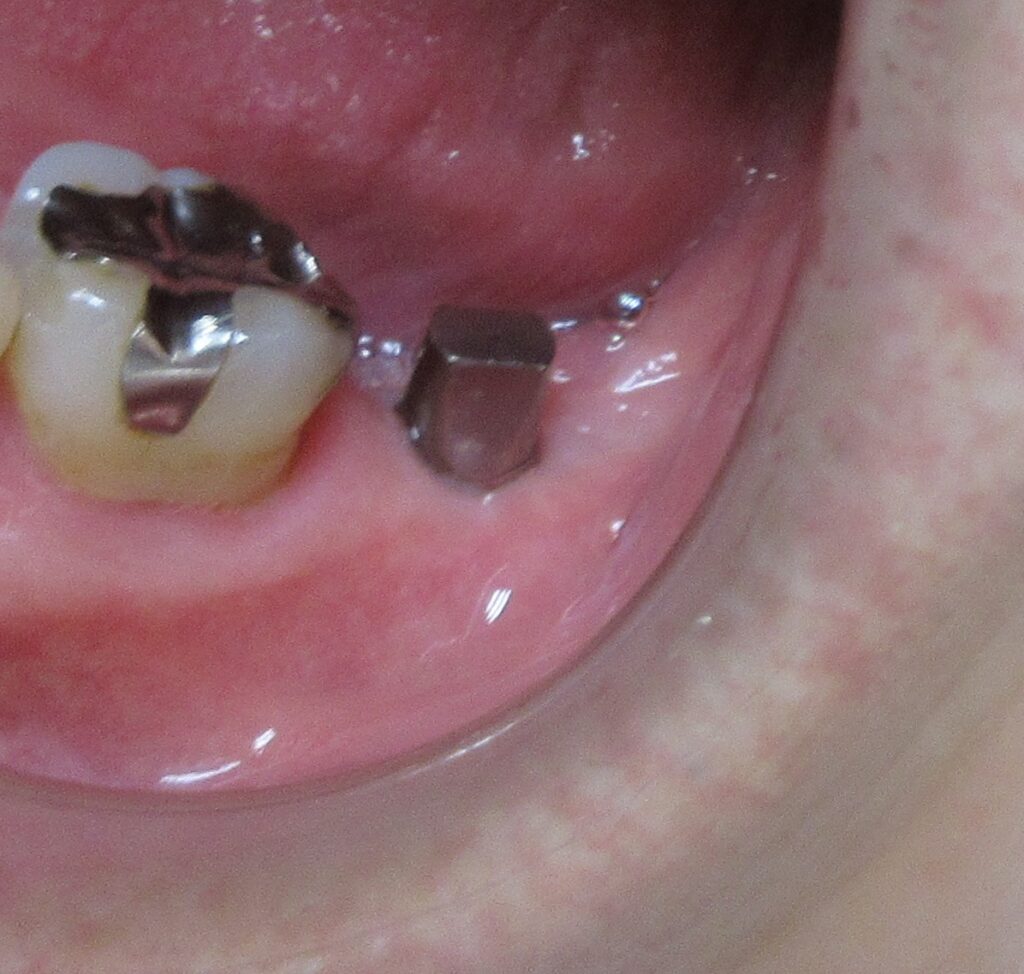

歯茎から骨の部分までを穴開けパンチの要領で穴を開けていきます。

くりぬいた部分の歯肉を取り除き、次は骨に穴を開けていきます。

ドリルの先端を細い物から徐々に大きい物に変えながら、植立するインプラント体のネジの部分を除いた胴の部分の太さに合わせた大きさの穴を開けていきます。